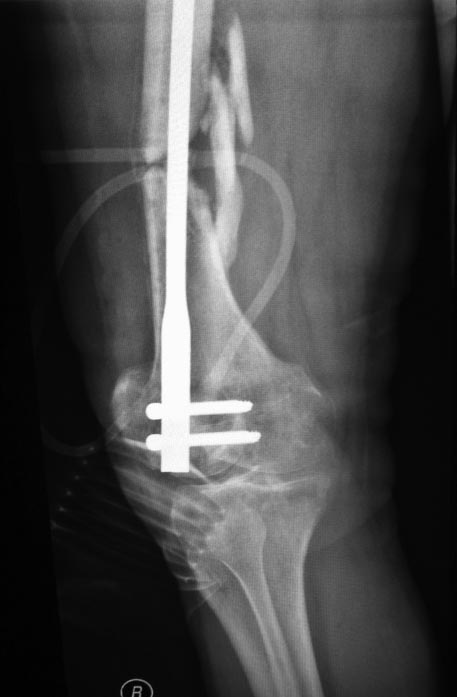

Доброго времени суток . Больной ( 35лет ) дважды оперирован после ДТП от марта 2012 пластинами с угловой стабильностью в том числе мостовидной мыщелковой пластиной . Обе конструкции сломал при этом соблюдал предписаный режим. 2 недели назад прооперирован в одной из клиник Санктпетербурга . укорочение минимальное 1 см ротационных смещений нет .Коленный сустав перестал сгибаться . Что делать дальше . больной морально и финансово истощен . ждать сращения а затем вставать на квоту на эндопротезирование коленного сустава .сейчас БОМБЕЙСКАЯ мсэ дала 3 гр инвалидности . РАботать мужчина не может . Не спрашиваю кто виноват ,что делать дальше .

еще снимки

1. Боковая проекция где?

2. Удалить гвоздь и ресинтезировать адекватно с исправлением оси и заходом через межмыщелковую вырезку. Как исправлять ось - на форуме много раз обсуждалось: можно в аппарате, можно с помощью поллеров.

P.S. после такого синтеза суставу определенно кирдык. (Извините за жаргон, но через латеральный мыщелок ввести ретроградный гвоздь...) Здесь можно было и антеградно сделать, не "вскрывая" сустав.

Гвоздь в суставе стоит - с чего бы ему(суставу) сгибаться...